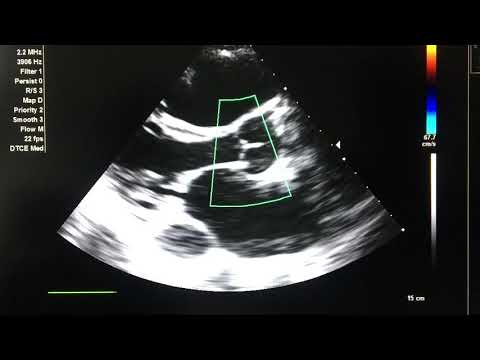

Post ASD Closure ECHO